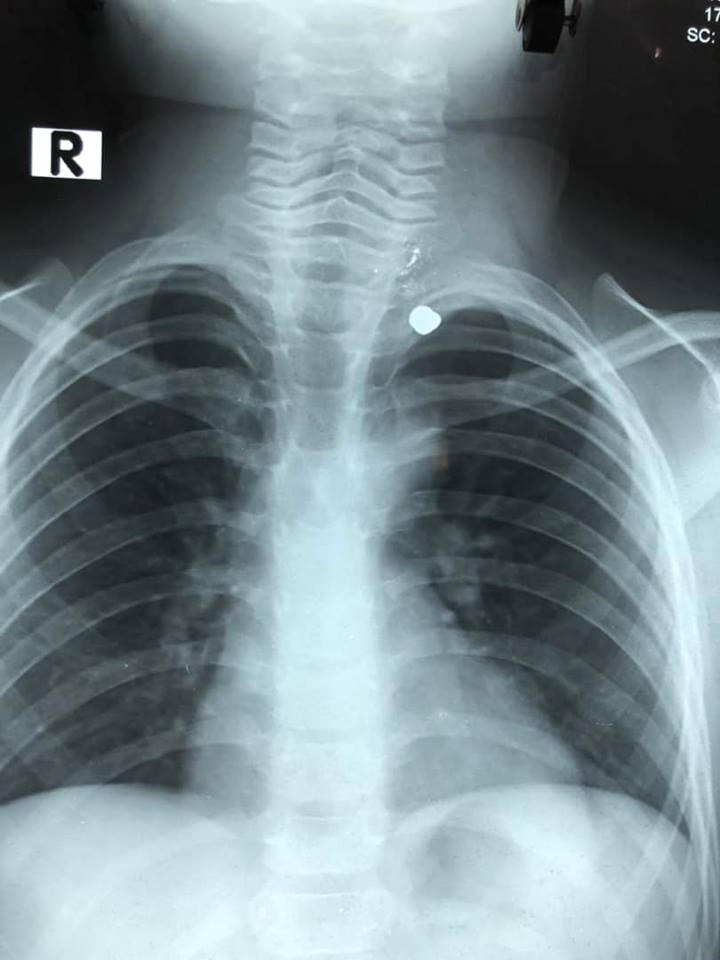

Viên đạn ở lồng ngực bé 6 tuổi qua kết quả chụp phim.

Tại Khoa Cấp cứu, bé được thăm khám, chụp X Quang ngực. May mắn, đạn đi từ cổ đến đỉnh phổi trái nhưng không xuyên vào mạch máu lớn, khí quản hay tim. Sau đó, bé được đưa vào Khoa Ngoại tổng hợp.